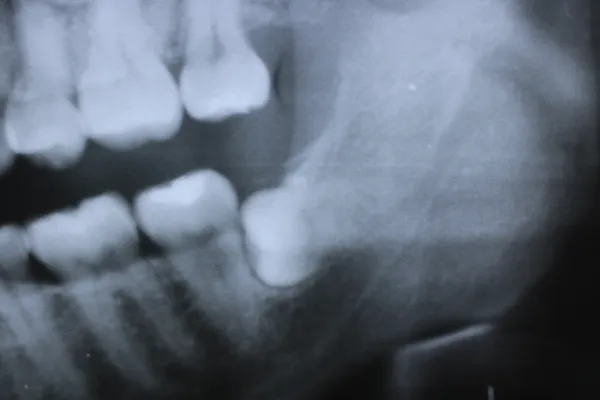

6入れ歯にしないブリッジ治療【ケース1】

H20.6.2のレントゲン

歯槽膿漏の為、上の6本の歯を抜き、上の右端から左端まで繋げたブリッジを作りました。

H31.1.25のレントゲン

H21.2.21に上の歯(ブリッジ)が完成しました。

左の写真は10年ちょっと経過したH31.1.25日に撮影した写真で、経過良好と思われます。

下顎も虫歯と歯槽膿漏のため長く持たせるために左下奥歯の一本を抜歯し残りを繋げて作りました。